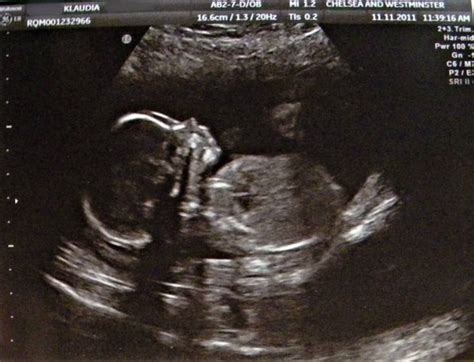

Tünetei a hüvelyi vérzés a terhesség első harmadában, fokozott terhességi hányinger, hányás, ami miatt a terhes az esetek 10%-ában már koraterhességben kórházi ápolásra szorul. Mindkét oldali petefészekben ún. tékasejtes ciszta alakul ki a méhlepény által termelt HCG-hormon fokozott jelenléte miatt. A fizikális vizsgálat során a számítottól eltérő nagyságú méh tapintható, és a nyakcsatornából vérzés látható. Ultrahang-vizsgálat során, a méhüregben a szőlőfürtszerű képlet jellegzetes "hóviharszerű" képet mutat. Curettage és szövettani vizsgálat a diagnózist pontosíthatja.